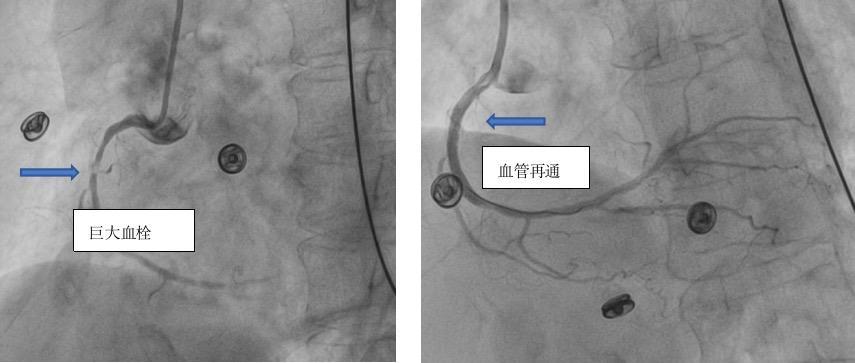

林忠伟介绍,冠脉造影提示,伍阿姨的冠状动脉存在多支血管病变、严重狭窄,危险性极高,猝死风险很大,其中右冠状动脉中段可见局部巨大血栓影,血管几乎完全闭塞,结合心电图,考虑右冠状动脉为“罪犯”血管。

20:30,手术团队为伍阿姨进行了球囊扩张术。20:34,于右冠状动脉植入支架一枚。术后伍阿姨胸闷缓解。门球时间(D-To-B)仅为44分钟。